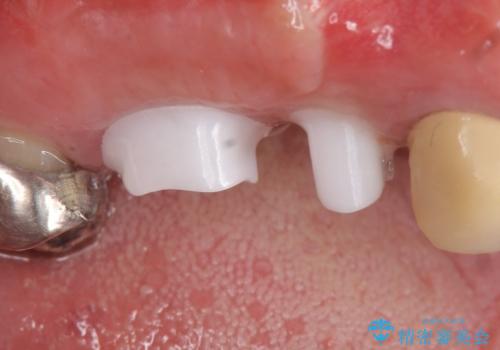

右上の567ブリッジを外したところ、右上5は歯根破折により保存不可能だったため、右上56部にインプラントを埋入し欠損補綴を行いました。

また右上5部に関しては抜歯時に歯槽堤保存術(抜歯窩に人工骨の填入を行う手術)を行い、骨の欠損を最小限に止めています。

カスタムアバットメントは患者様それぞれの歯茎に合わせて製作されたオーダーメイドのアバットメントです。

既製のアバットメントに比べ適合がよく、高い清掃性を誇ります。